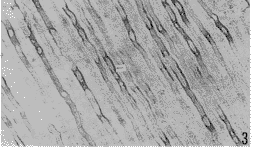

在牙髓中央区,纤维粘连蛋白-IR以条索状和网状两种形式存在,条索状者一般纤维粗大,数量少,多局限于中轴部分,沿血管和神经分布,动脉周围多于静脉。网状者一般较条索状纤维细小,数量多,广泛存在于中轴以外的基质中。从中轴向周边,纤维由粗变细,和致密(图1)。在多细胞区纤维粘连蛋白-IR物略为增粗,呈细条索网,经成纤维细胞之间至乏细胞区。在乏细胞区纤维粘连蛋白-IR物更为细小,无方向性,彼此交织成网,并向成牙本质细胞层延伸。在成牙本质细胞层,纤维粘连蛋白-IR物汇集成束,经成牙本质细胞之间到达前期牙本质(图2)。前期牙本质内的纤维粘连蛋白-IR物尤为丰富,纤维粗大密集,着色深;在成熟牙本质内,纤维粘连蛋白-IR物仅见于牙本质小管与成牙本质细胞突起之间的间隙内,通过小管侧支与相邻牙本质小管内的纤维粘连蛋白-IR物相连。其他成熟牙本质内未见纤维粘连蛋白阳性反应(图3)。用PBS液代替一抗的对照片中未见纤维粘连蛋白的阳性反应物。

图3 成熟牙本质内纤维粘连蛋白(↑)行于牙本质小管壁和成牙本质细胞突起之间. ×400

Fig.3 The Fibronectin(↑) in the space between the walls of dentinal tubules and the process of the odontoblast in mature dentin. ×400